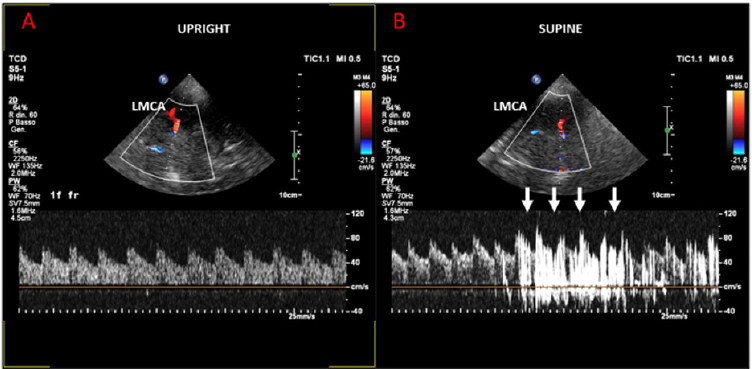

images. Thus, a cTCD with the administration of activated saline

was performed and the left middle cerebral artery (LMCA) was

monitored through the temporal bone window. In supine position,

no passage of echo-contrast was observed in the LMCA (Figure 1A).

In the upright position, however, a high number of hits appeared

in the LMCA, consistent with the occurrence of a paradoxical large

shunt at the level of the PFO (Figure 1B). Finally, a right heart

A) Supine position: no passage of echo-contrast was observed in the LMCA.

B) Upright position: a significant number of hits in the LMCA, consistent for a paradoxical shunt at the level of a large PFO.